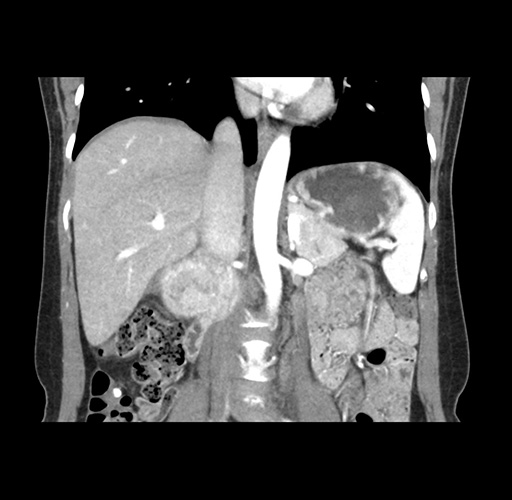

Imaging Analysis

Look through the patient's CT scan to identify any areas of concern for the necessary procedure.

Based on your CT findings, which issue(s) would give reason for "planned slowing down moment(s)" in this case?

Considering a standard left lateral sectionectomy procedure, what step(s) of the operation would you do differently in this case ?